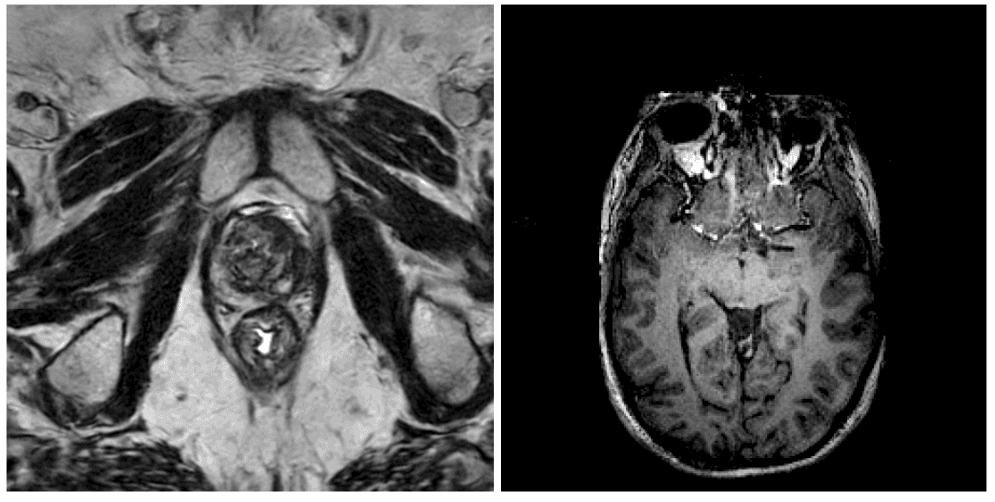

NVIDIA has released a brain MRI generation model on the Hugging Face platform. The model is a 3D latent diffusion model capable of synthesizing high-resolution brain scans across four key MRI modalities: T1-weighted, FLAIR (Fluid-Attenuated Inversion Recovery), T2-weighted, and SWI (Susceptibility Weighted Imaging). According to the announcement, the model achieves state-of-the-art Fréchet Inception Distance (FID) scores—a metric for evaluating the quality and diversity of generated images—and operates with 33× faster inference speed compared to previous approaches.

Generative AI for medical imaging, particularly 3D data like MRI scans, presents significant technical challenges beyond 2D image generation. Models must produce anatomically plausible 3D volumes across multiple contrasting modalities that are clinically useful. Applications include data augmentation for training diagnostic AI systems, creating synthetic datasets for research while protecting patient privacy, and educational simulation.

Latent diffusion models have become a dominant architecture for high-quality image synthesis. Adapting them to 3D medical data requires significant architectural and training innovations to handle the high dimensionality and memory constraints. NVIDIA's release indicates a focus on both quality (FID) and practical utility (inference speed), which are critical barriers for clinical and research adoption.